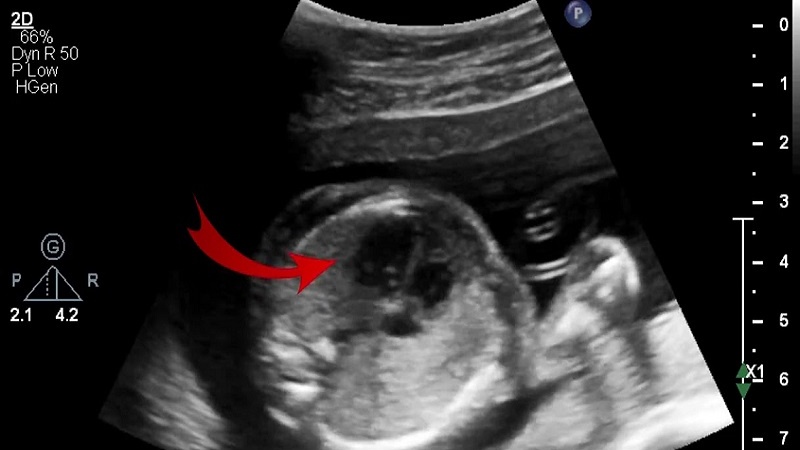

Trong y học, "nốt echo" hay "nốt phản âm" là thuật ngữ để mô tả các đám sáng xuất hiện trong hình ảnh siêu âm của tim. Những nốt echo này thường xuất hiện trong tim thai và có thể gây lo lắng cho phụ huynh khi được phát hiện trong quá trình siêu âm thai kỳ.

Trong y học, thuật ngữ "nốt echo" thường được sử dụng để mô tả một hiện tượng cụ thể trong quá trình kiểm tra hoặc siêu âm. Đây có thể là một sự phản chiếu của sóng âm trong cơ thể của bệnh nhân trong quá trình siêu âm. Khi sóng âm gặp phải một ranh giới hoặc một cấu trúc cụ thể trong cơ thể, nó sẽ phản chiếu lại và tạo ra một hình ảnh "nốt echo" trên hình ảnh siêu âm.

Nốt echo thường xuất hiện như các điểm sáng hoặc bóng trên hình ảnh siêu âm và có thể chỉ ra sự tồn tại của các cấu trúc bên trong cơ thể, chẳng hạn như các khối u, các cặp mô hoặc các cấu trúc tự nhiên khác. Điều này giúp các chuyên gia y tế đưa ra các đánh giá và chẩn đoán chính xác về tình trạng sức khỏe của bệnh nhân.